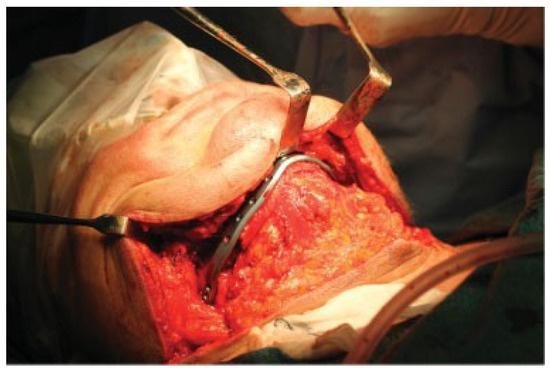

Figure 7.

Wide extra-oral exposure of the mandible, removal of plates and granular tissue in the fracture areas. Outcome model and PSI is displayed.